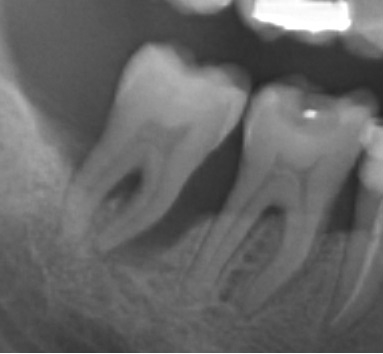

Bogata w płytki i leukocyty fibryna jest stosowana w regeneracji tkanek od ponad 15 lat. Pozytywny wpływ PRF (platelet-rich fibrin) na regenerację tkanek miękkich jest niewątpliwy, bezsporny i częściowo udowodniony w badaniach klinicznych i analizach biochemicznych. Wpływ PRF na regenerację tkanki kostnej jest obserwowany klinicznie, ale nadal niedostatecznie poznany jest mechanizm tego zjawiska.

Platelet- and leukocyte-rich-fibrin has been used in regeneration of tissue for more than 15 years. The positive influence of PRF on the regeneration of soft tissue is undoubtedly, without question and partially proven in clinical studies and biochemical analysis. Influence of PRF on regeneration of bone tissue is observed clinically but the mechanism of this phenomenon is still not sufficiently known.